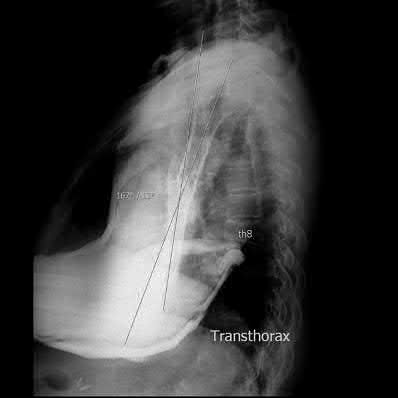

A 33-year-old secretary presents three months after a motor vehicle collision with a mild asymmetry to her sternal area and difficulty swallowing. She denies any complaints of respiratory distress or upper extremity paresthesias. Her upper extremity neurovascular exam shows no deficits. A 3-D computed tomography image is shown in Figure A. What is the most appropriate treatment for this patient?

The clinical presentation is consistent with a chronic sternoclavicular dislocation, which is defined as being greater than 3 weeks old. The 3D CT image shows posterior displacement of the medial clavicle relative to the sternum. Chronic anterior dislocations are recommended to be treated conservatively, especially if not symptomatic, but as this is a posterior dislocations, current recommendations are to treat them with reduction in order to avoid delayed issues with the medial clavicle interacting with the mediastinal structures.

The review article by Wirth and Rockwood notes the following complications with posterior dislocation: respiratory distress, venous congestion or arterial insufficiency, brachial plexus compression, and myocardial conduction abnormalities. They recommend reconstruction of the costoclavicular ligaments with resection of the medial claviclar head as needed for unstable or symptomatic injuries.